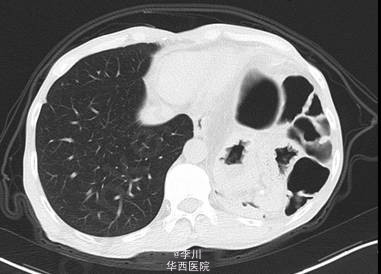

患者男,49岁9月,因“ 全腹胀痛14天,加重伴呕吐4天”入院。患者14天前在进食“甜酒”后出现腹部胀痛,逐渐扩大到整个腹部,伴恶心干呕,不伴寒战发热、腹泻、晕厥,无心悸、气促、发绀。外院诊断“肠梗阻”,予以石蜡油灌肠及输液治疗后缓解。4天前患者在进食后出现同前症状,遂于我院就诊。

既往患者1+年前因摔跤撞伤腹部,于贵阳医学院行“脾切除+膈疝修补术”。查体左肺呼吸音减弱,可问及异常肠鸣音。CT提示:左侧膈面上抬、局部膈肌软组织似不连续,可见胃及部分肠管上移,膈疝?